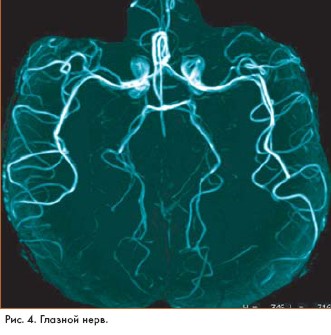

Магнитно-резонансные изображения (magnetic resonance imaging - MRI), полученные на основе высокоскоростного сканирования с помощью технологии GE Excite, открывают новые возможности хорошо известного метода исследования. Идея была представлена на 10-й научной конференции Международного общества Magnetic Resonance in Medicine, которая прошла в США.

Система GE Excite была разработана компанией GE Medical Systems (США). Высокая скорость сканирования и компьютерной обработки данных позволяет получать объемные MR-изображения высокого разрешения в реальном времени, например в процессе работы сердца.

"Мы впервые получили возможность получать изображения в процессе реальной жизнедеятельности органов, - говорит доктор Lawrence Tanenbaum из Института неврологии Нью Джерси (США). - GE Excite не требует задержки дыхания в процессе исследования больных и особенно удобна для получения качественных изображений органов, находящихся в движении, например сердца и сосудистой системы"